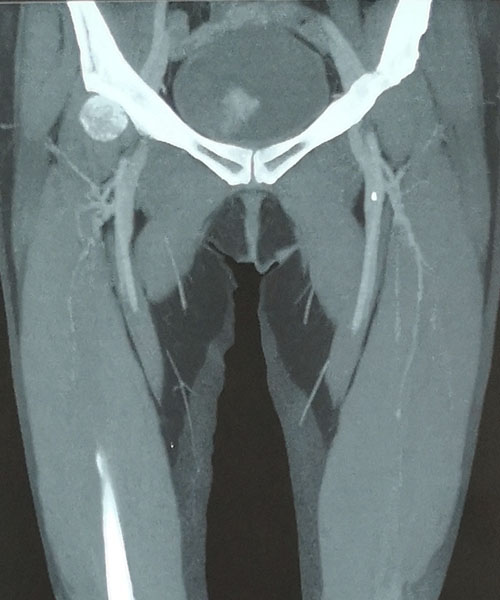

术后DSA评估导管尖端位置

本例患者由于是双侧乳腺癌术后伴双侧颈部及左胸壁广泛转移而来我院就诊,难以建立常规输液通路。乳腺中心回天立主管医生通过查阅大量文献资料并结合既往手术经验,与宋振川主任反复商讨后制定了股静脉港的置入方案。手术当日,在超声科纪晓惠主任、放射科杨光主任的协助下,成功将导管送达下腔静脉与右心房结合部,港座埋置于右下腹壁皮下,完成了我省首例股静脉穿刺静脉港置入术。术后第一天患者恢复顺利,下床活动良好,静脉通路顺畅。